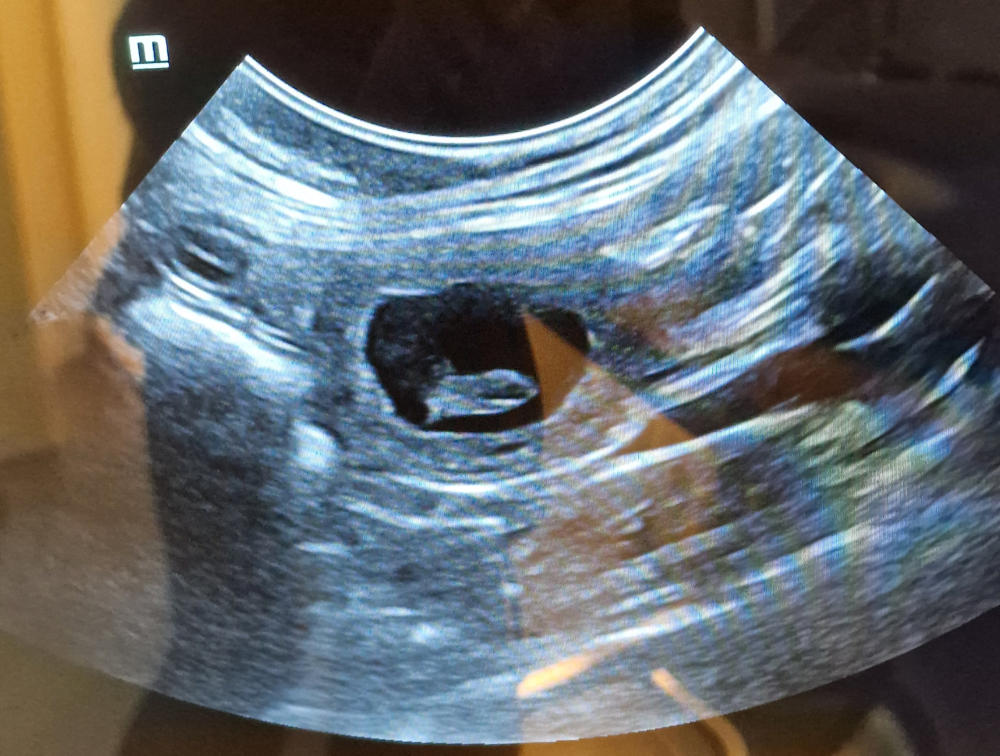

Weitere 4 Wochen sind vergangen und unser Frauli

war mit Mala bei unserer Tierärztin „Baby‘s gucken“.

Wir hatten es ja schon fast vermutet, da sie nur noch

durch die Gegend walzt und wir sie seit gut einer

Woche auch die Treppe rauf- und runter tragen. „Die

Hütte ist voll!!!“ Grins. Könnt ihr die Zwergis zählen?

Alles ist für die Geburt vorbereitet. Unser Frauli sagt ja, „es werden Sonntagsbabys“. Mal schauen,

ob sie Recht behält. Wir melden uns wieder, sobald unsere Kühchen „auf der Weide grasen“. Smile.